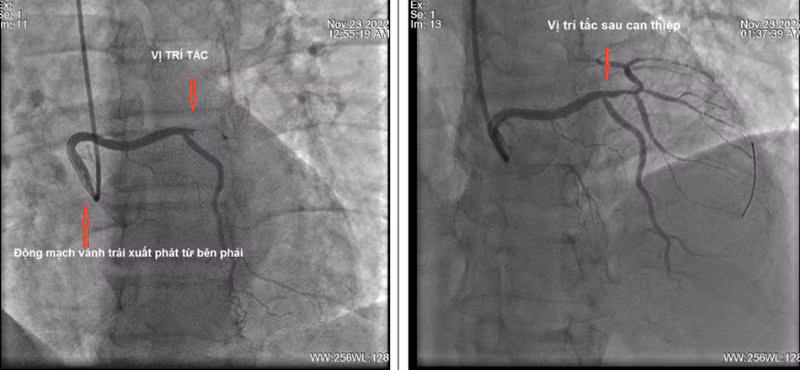

Hình ảnh chụp động mạch vành trước và sau khi can thiệp. Ảnh: BV.

Sau khi được xử trí cấp cứu ban đầu, bệnh nhân được đưa ngay vào phòng can thiệp mạch để chụp và can thiệp tái thông mạch vành bị tắc. Kết quả chụp động mạch vành lại cho thấy bệnh nhân có giải phẫu động mạch vành trái xuất phát rất bất thường.

Động mạch vành trái bị tắc hoàn toàn một nhánh rất lớn, nhưng động mạch này không xuất phát bình thường từ xoang vành trái mà lại xuất phát từ xoang vành phải. Đây là một trường hợp rất hiếm gặp, gây nhiều khó khăn khi chụp và can thiệp động mạch vành do các ống thông chụp động mạch vành trái thông thường không thể tiếp cận được lỗ vào của động mạch vành trái.

Kíp kỹ thuật đã hội chẩn và quyết định sử dụng loại ống thông can thiệp dành cho động mạch vành phải và kết hợp với một loại ống thông chuyên dụng nhỏ hơn đi bên trong để tiếp cận động mạch vành trái.

Cuối cùng, sau khi đã tiếp cận được lỗ vào động mạch vành trái, nong chỗ tắc bằng bóng thì các nhánh động mạch vành đều lưu thông máu tốt, bệnh nhân đỡ đau ngực ngay sau thủ thuật.